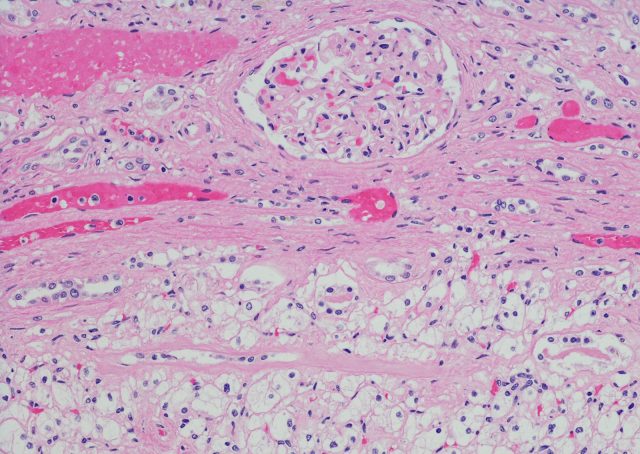

MedikuntzaMatematikak, histopatologiak eta genomikak bat egin dute giltzurruneko minbiziaren ikerketan. UPV/EHUko Annick Laruelle Ikerbasque irakasleak egin du ikerlana, eta zelula argiko giltzurrun-kartzinoma erasokorrak aztertu ditu. Laruellek ondorioztatu du matematikan oinarritzen direla tumore barneko heterogeneotasunaren funtsetako batzuk, eta tumore barneko heterogeneotasun-maila txikiagoa dela berretsi du kartzinoma mota horretan. Azalpenak Zientzia Kaieran.